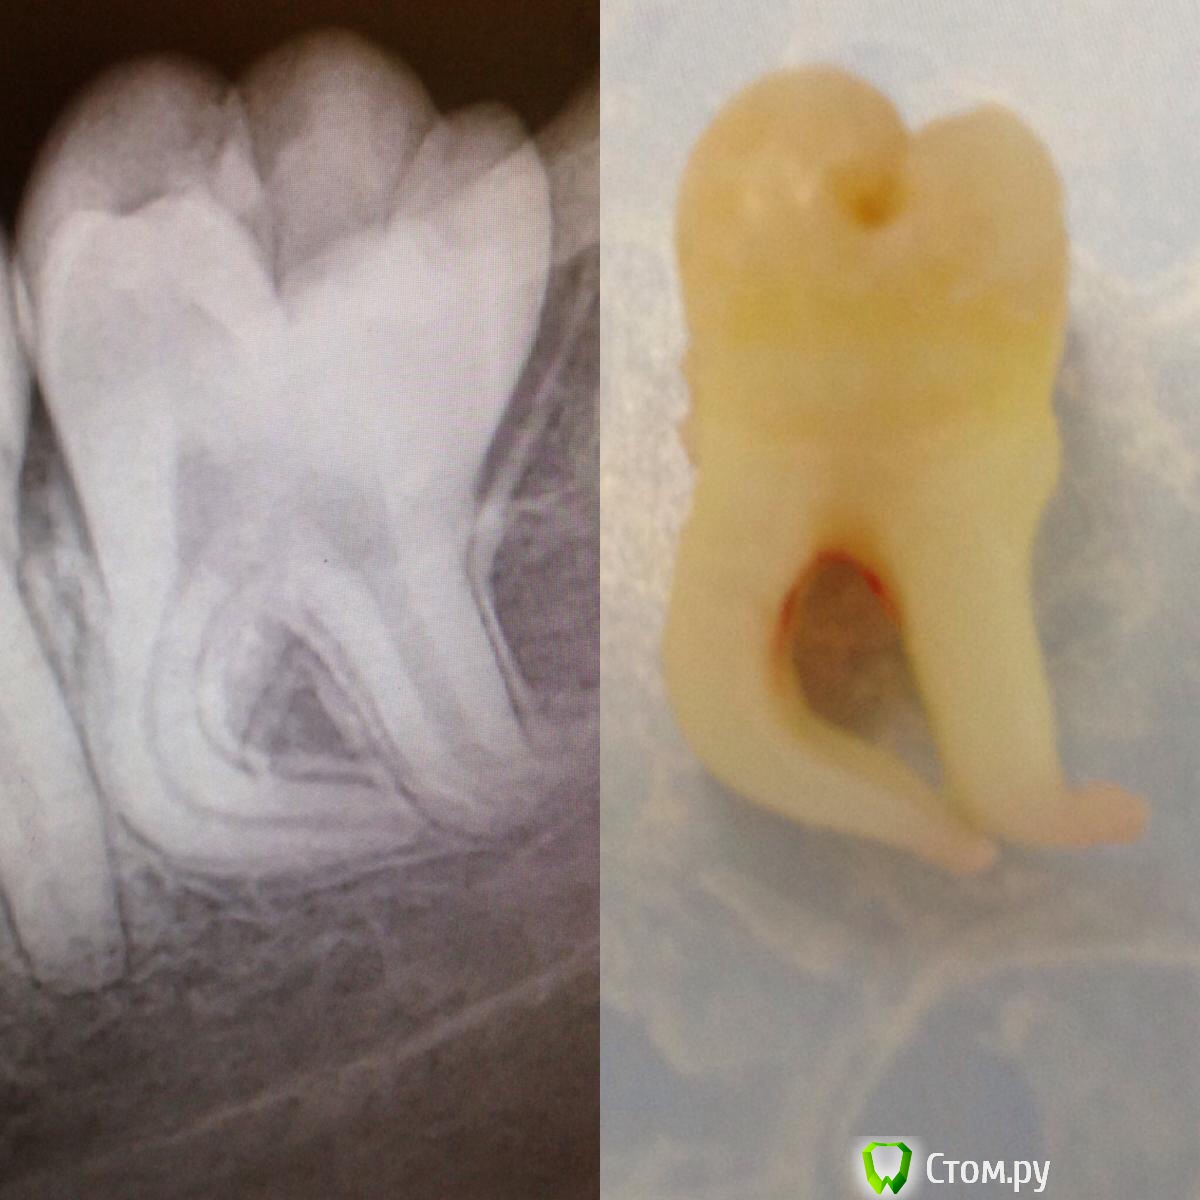

IvanK Опубликовано 10 декабря, 2013 Автор Поделиться Опубликовано 10 декабря, 2013 Разжиревшая годзила... Это шапка Петрушки, так назвала этот зуб ассистент )) 1 Ссылка на комментарий

komar56 Опубликовано 10 декабря, 2013 Поделиться Опубликовано 10 декабря, 2013 Это шапка Петрушки, так назвала этот зуб ассистент )) Не согласен! 1 Ссылка на комментарий